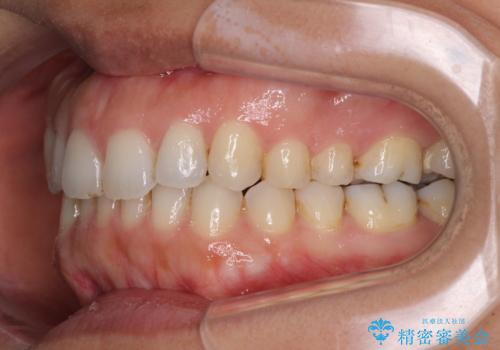

受け口傾向の前歯 すきっ歯の改善

- 前歯の隙間と口元の突出感を気にして来院された患者様です。

嚥下時に舌を突出させる癖があり、成長期に下顎が有意に成長し、歯と歯の間に隙間ができてしまいました。

舌の癖を改善し、インビザラインにて治療を行うこととしました。

舌癖を改善したことで、隙間や突出感を改善することができました。

隙間は後戻りしやすいため、舌側を細いワイヤーで固定することとしました。